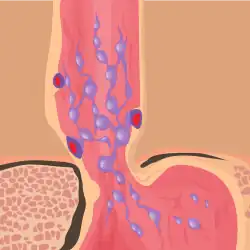

Esophageal varices are extremely dilated sub-mucosal veins in the lower third of the esophagus.[1] They are most often a consequence of portal hypertension,[2] commonly due to cirrhosis.[3] People with esophageal varices have a strong tendency to develop severe bleeding which left untreated can be fatal. Esophageal varices are typically diagnosed through an esophagogastroduodenoscopy.[4]

Normal portal pressure is approximately 9 mmHg compared to an inferior vena cava pressure of 2–6 mmHg. This creates a normal pressure gradient of 3–7 mmHg. If the portal pressure rises above 12 mmHg, this gradient rises to 7–10 mmHg.[5] A gradient greater than 5 mmHg is considered portal hypertension. At gradients greater than 10 mmHg, blood flowing through the hepatic portal system is redirected from the liver into areas with lower venous pressures. This means that collateral circulation develops in the lower esophagus, abdominal wall, stomach, and rectum. The small blood vessels in these areas become distended, becoming more thin-walled, and appear as varicosities.

Varices can also form in other areas of the body, including the stomach (gastric varices), duodenum (duodenal varices), and rectum (rectal varices). Treatment of these types of varices may differ. In some cases, schistosomiasis also leads to esophageal varices.